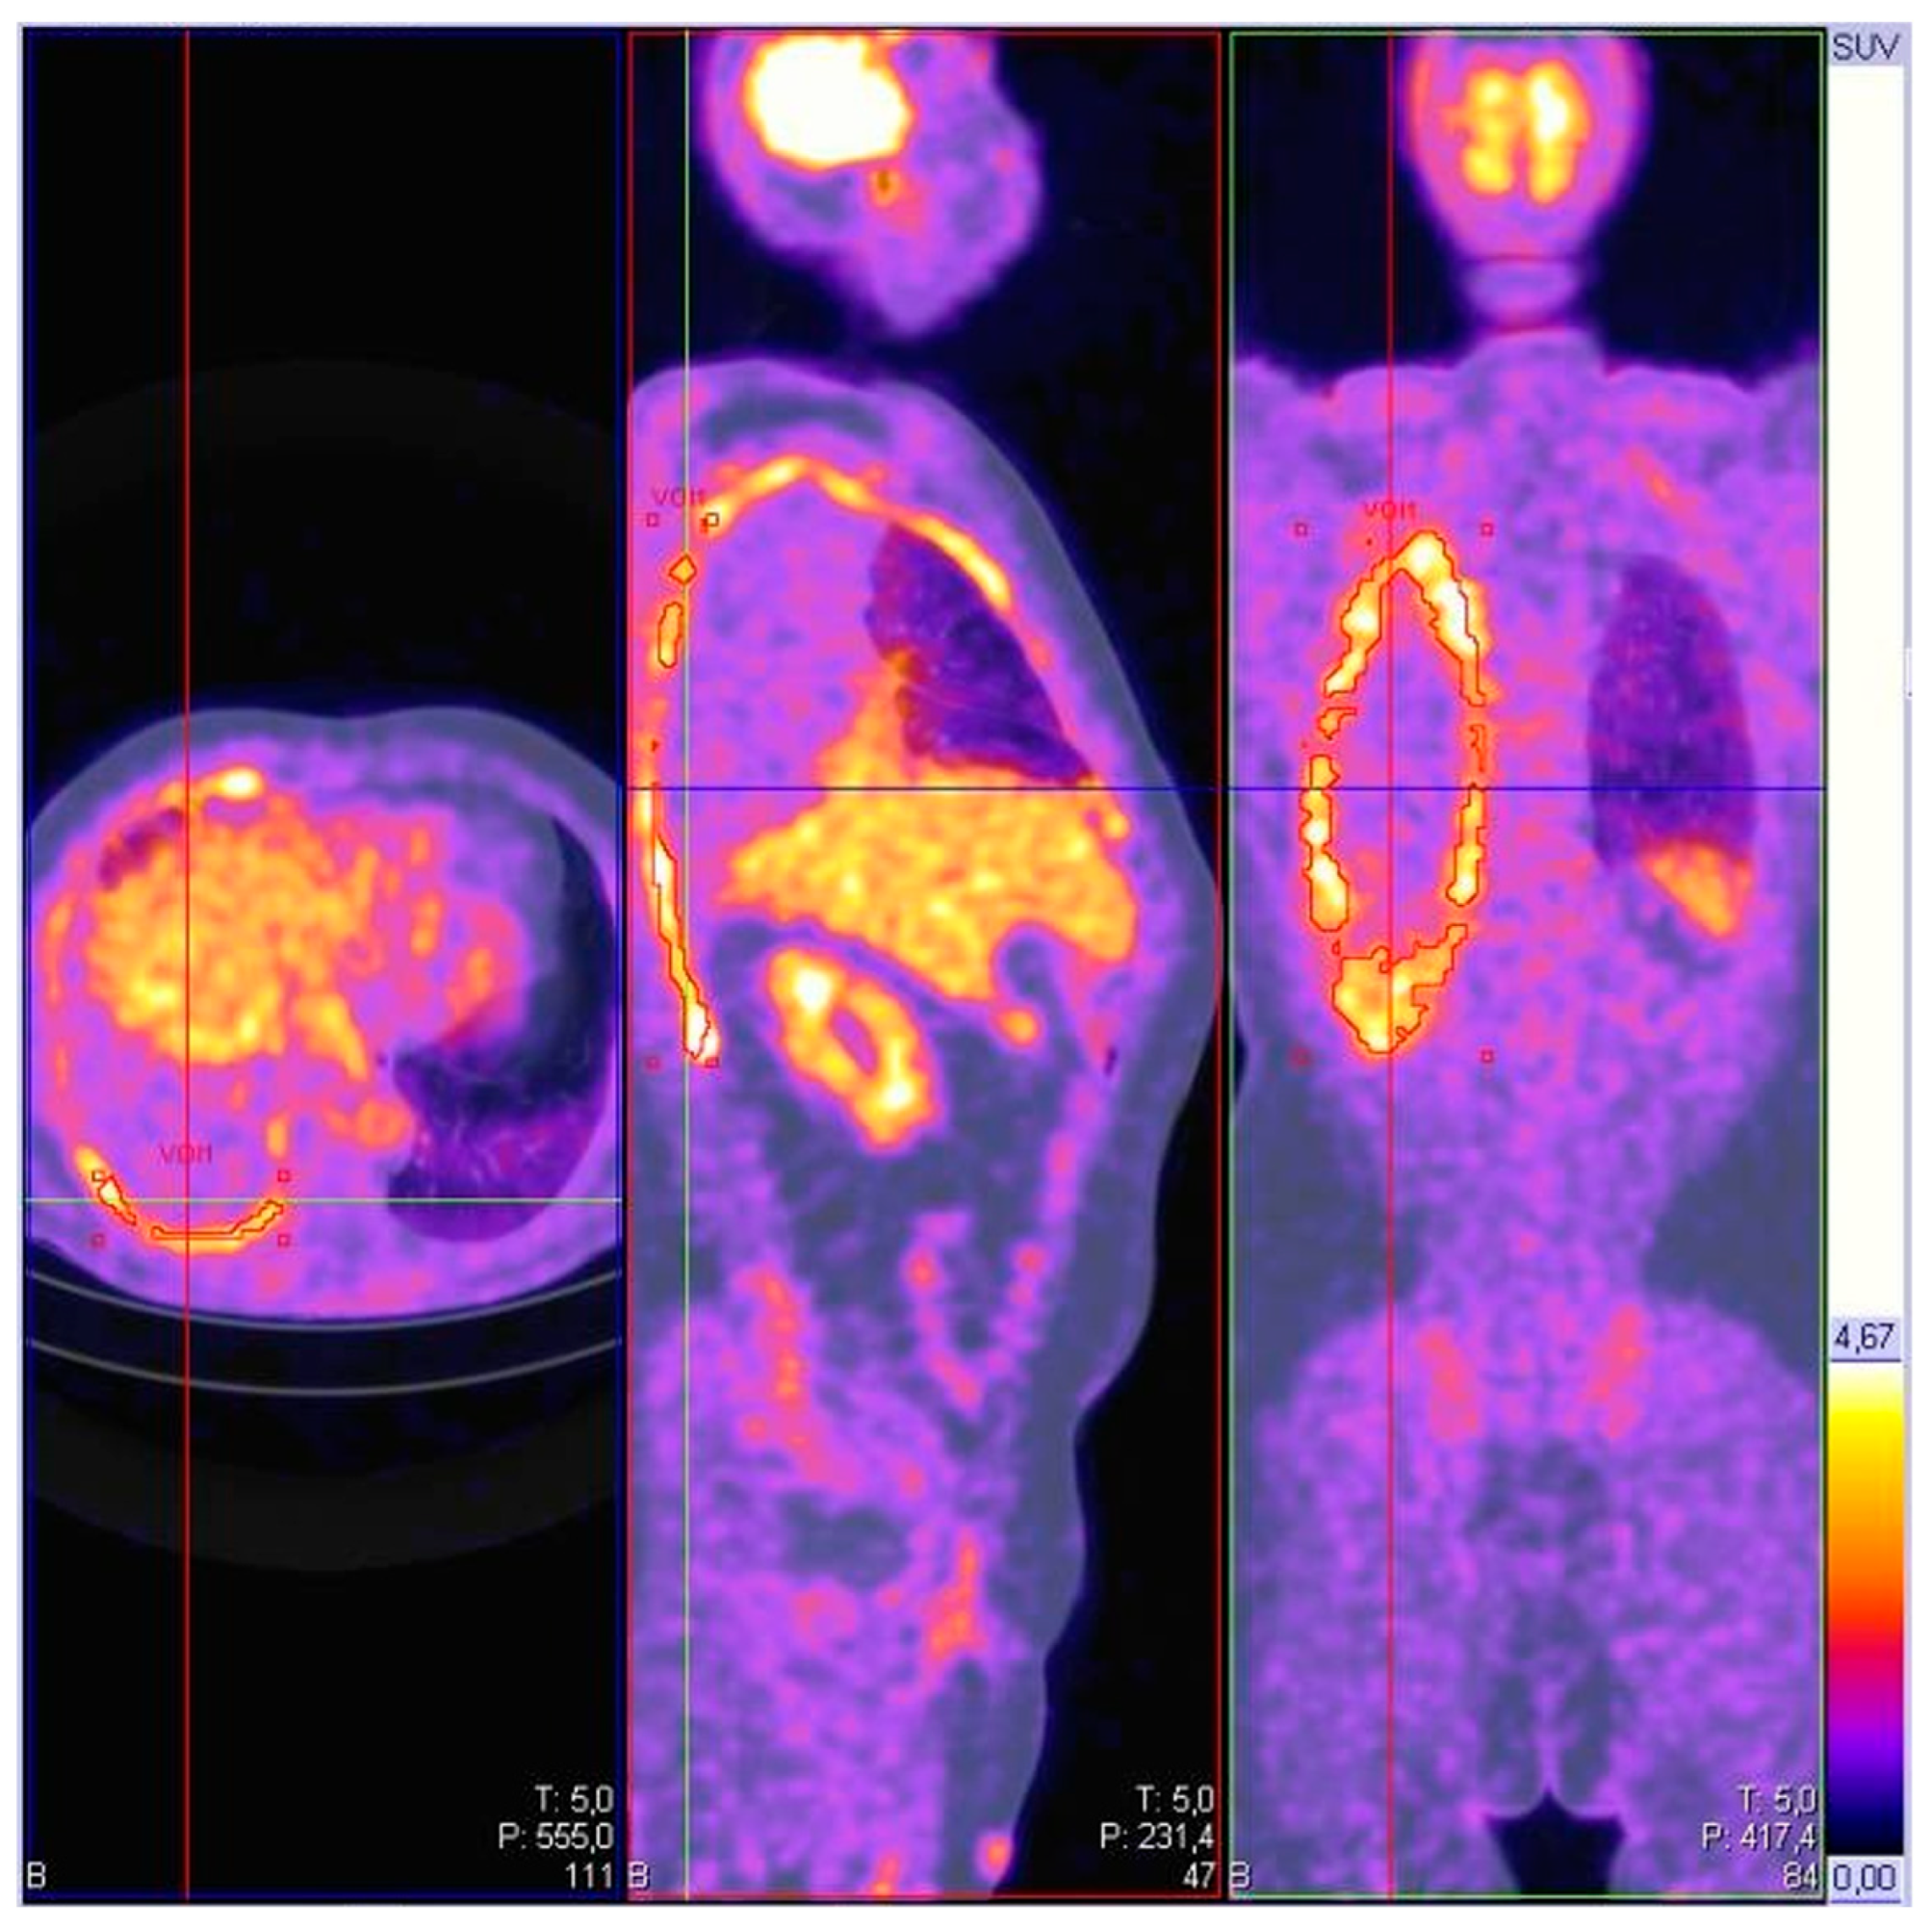

5.4. Positron Emission Tomography